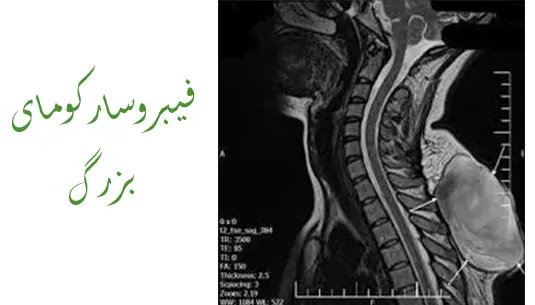

تشخیص فیبروسارکوما معمولاً از طریق روشهای تصویربرداری مانند CT اسکن یا MRI انجام میشود که به پزشک کمک میکند محل دقیق تومور و میزان گسترش آن را شناسایی کند. برای تأیید تشخیص، ممکن است پزشک از بیوپسی نیز استفاده کند، که در آن نمونهای از بافت تومور برداشته شده و تحت میکروسکوپ بررسی میشود تا نوع سلولها و تومور مشخص شود.